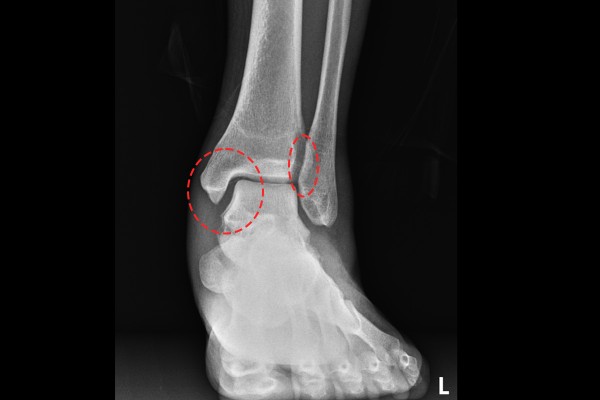

환자분의 발목 상태 파악을 위해 X-RAY 사진을 살펴보면, 먼저 증상이 없는 오른쪽 발목은 발목관절의 내측 공간이 벌어지지 않았고, 아래 거골과 위쪽 경골 부분이 딱 맞아 보이고, 경골과 비골 사이에 겹치는 부분이 정상적으로 확인됩니다.